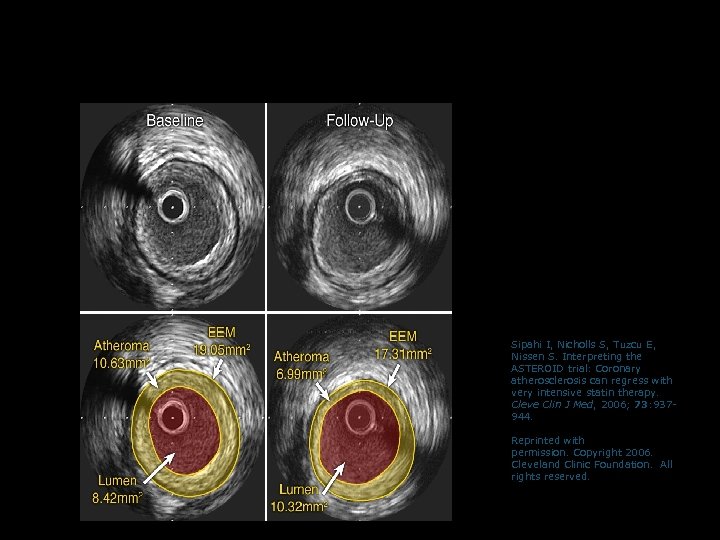

Example of Regression of Atherosclerosis with Rosuvastatin in ASTEROID (measured by IVUS) Sipahi I, Nicholls S, Tuzcu E, Nissen S. Interpreting the ASTEROID trial: Coronary atherosclerosis can regress with very intensive statin therapy. Cleve Clin J Med, 2006; 73: 937944. Reprinted with permission. Copyright 2006. Cleveland Clinic Foundation. All rights reserved.